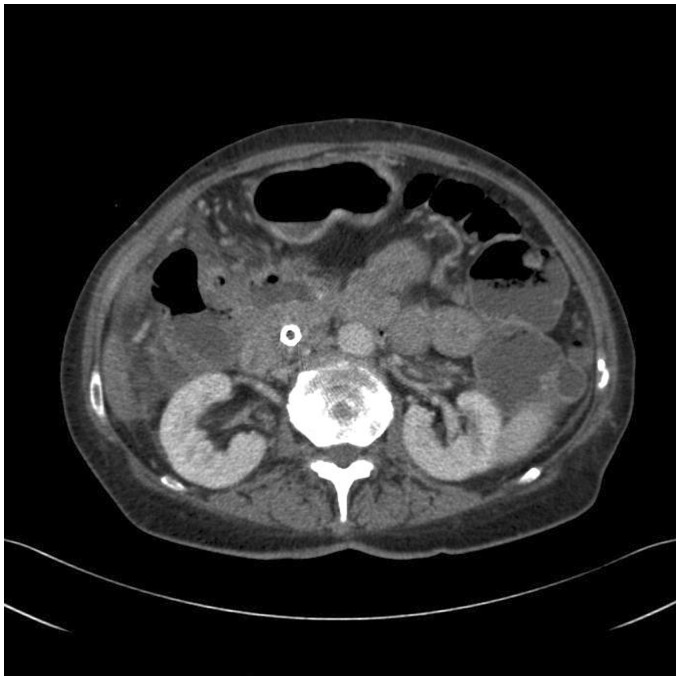

不可逆电穿孔(IRE)是一种消融技术,正在被研究作为胰腺癌的潜在治疗方法。然而,许多患者在胆管内放置金属支架,这被认为是IRE消融术的禁忌症。我们报告一个病例,在胰腺头部区域IRE消融术对患者进行金属支架导致严重的并发症。治疗后,患者出现了多种并发症,包括十二指肠穿孔和横结肠穿孔,以及肠系膜上动脉分支出血,最终导致患者死亡。因此,我们认为如果考虑在金属支架附近进行IRE消融,了解这一点是很重要的。

Irreversible electroporation (IRE) is an ablation technique that is being investigated as a potential treatment of pancreatic cancer. However, many of these patients have a metallic stent in the bile duct, which is recognized as a contraindication for IRE ablation. We report a case in which an IRE ablation in the region of the pancreatic head was performed on a patient with a metallic stent which led to severe complications. After the treatment, the patient suffered from several complications including perforation of the duodenum and transverse colon, and bleeding from a branch of the superior mesenteric artery which eventually lead to her death. Therefore, we believe it is important to be aware of this if an IRE ablation close to a metallic stent is considered.